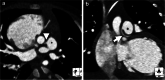

Imaging the coronary arteries of children, with their faster heart rates, small vessel size and common inability to lie still or breath-hold, has been a major challenge. With numerous advances in technology, CT examinations can now be performed quickly, often with children free-breathing and with much lower radiation doses than previously. This has led to increased use in children. Care must be taken with technique and choice of electrocardiogram (ECG)-gating technique to obtain adequate imaging for a diagnosis while keeping radiation dose as low as reasonably achievable (ALARA). In this paper, we discuss techniques and tips for CT imaging of the coronary arteries in children, including use of dual-source- and ultrawide-detector CT scanners.